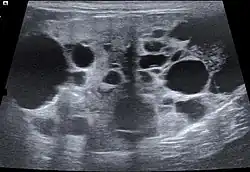

| Polycystic kidney disease | Hereditary cystsformation in Persian cats |

The ultrasound examination allows morphological changes in the kidneys in more detail. In addition to changes in size and shape, renal cysts, localized (focal) organ damage, water sac kidneys and urinary retention as well as tumors can also be visualized. Hardly defined (diffuse) organ changes are accompanied by changes in echogenicity, but can only rarely be assigned to defined diseases.[22] Pulsed Wave Doppler" can also be used to detect circulatory disorders.[23] Calcification (nephrocalcinosis) is also common in chronic kidney disease and can also be detected sonographically.[24]